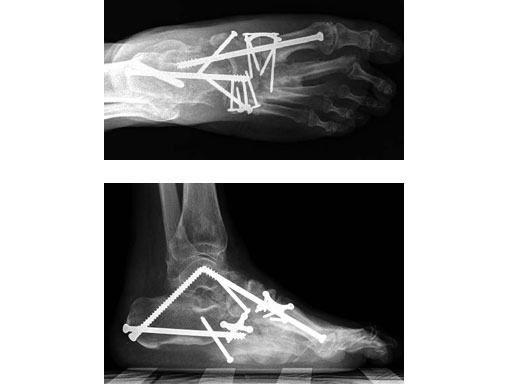

Case 1: 47-year-old female

Case provided by Andrew K Sands, New York, USA

Charcot foot treated with MFB and X-plate